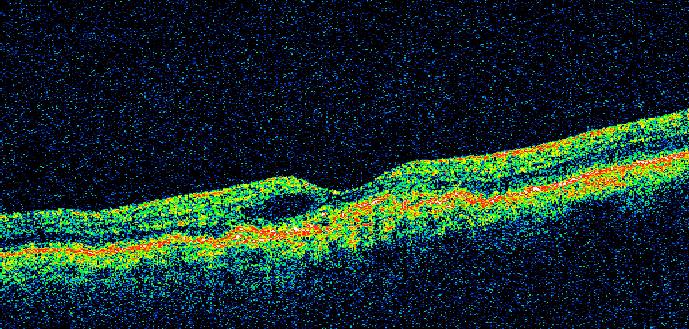

Santo Domingo, RD. – La Academia de Ciencias de la República Dominicana, a través de su Comisión de Ciencias de la Salud, anunció la proyección del video titulado “Enfermedades maculares y su impacto”, una iniciativa orientada a educar y sensibilizar a la población sobre las afecciones que afectan la mácula y su repercusión en la calidad de vida.

La actividad contará con los comentarios especializados de la Dra. Niurka Leonor y el Dr. Juan Ubiera, quienes abordarán los principales aspectos clínicos, preventivos y sociales relacionados con las enfermedades maculares. La moderación estará a cargo del Dr. Herbert Stern, coordinador de la Comisión de Ciencias de la Salud de la institución.

Con esta iniciativa, la Academia reafirma su compromiso con la promoción del conocimiento científico y la orientación a la ciudadanía en temas de salud pública, especialmente en lo relativo a la prevención y detección temprana de enfermedades que pueden comprometer la visión.